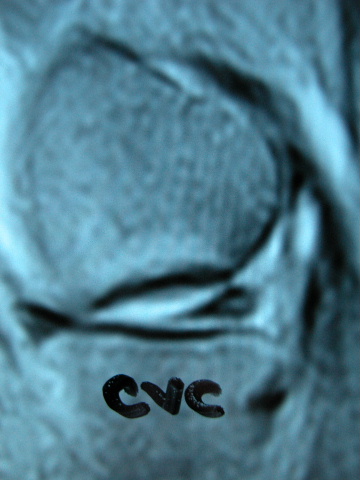

ACT Osteonecrosis de rodilla. RM.